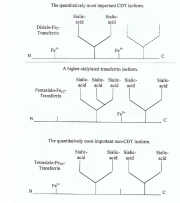

| 16:57, 29 בפברואר 2016 | Cdt2.png (קובץ) |  |

826 קילו־בייטים | Motyk | 1 | |

| 22:24, 28 בפברואר 2016 | Cdt1.png (קובץ) |  |

531 קילו־בייטים | Motyk | 1 | |